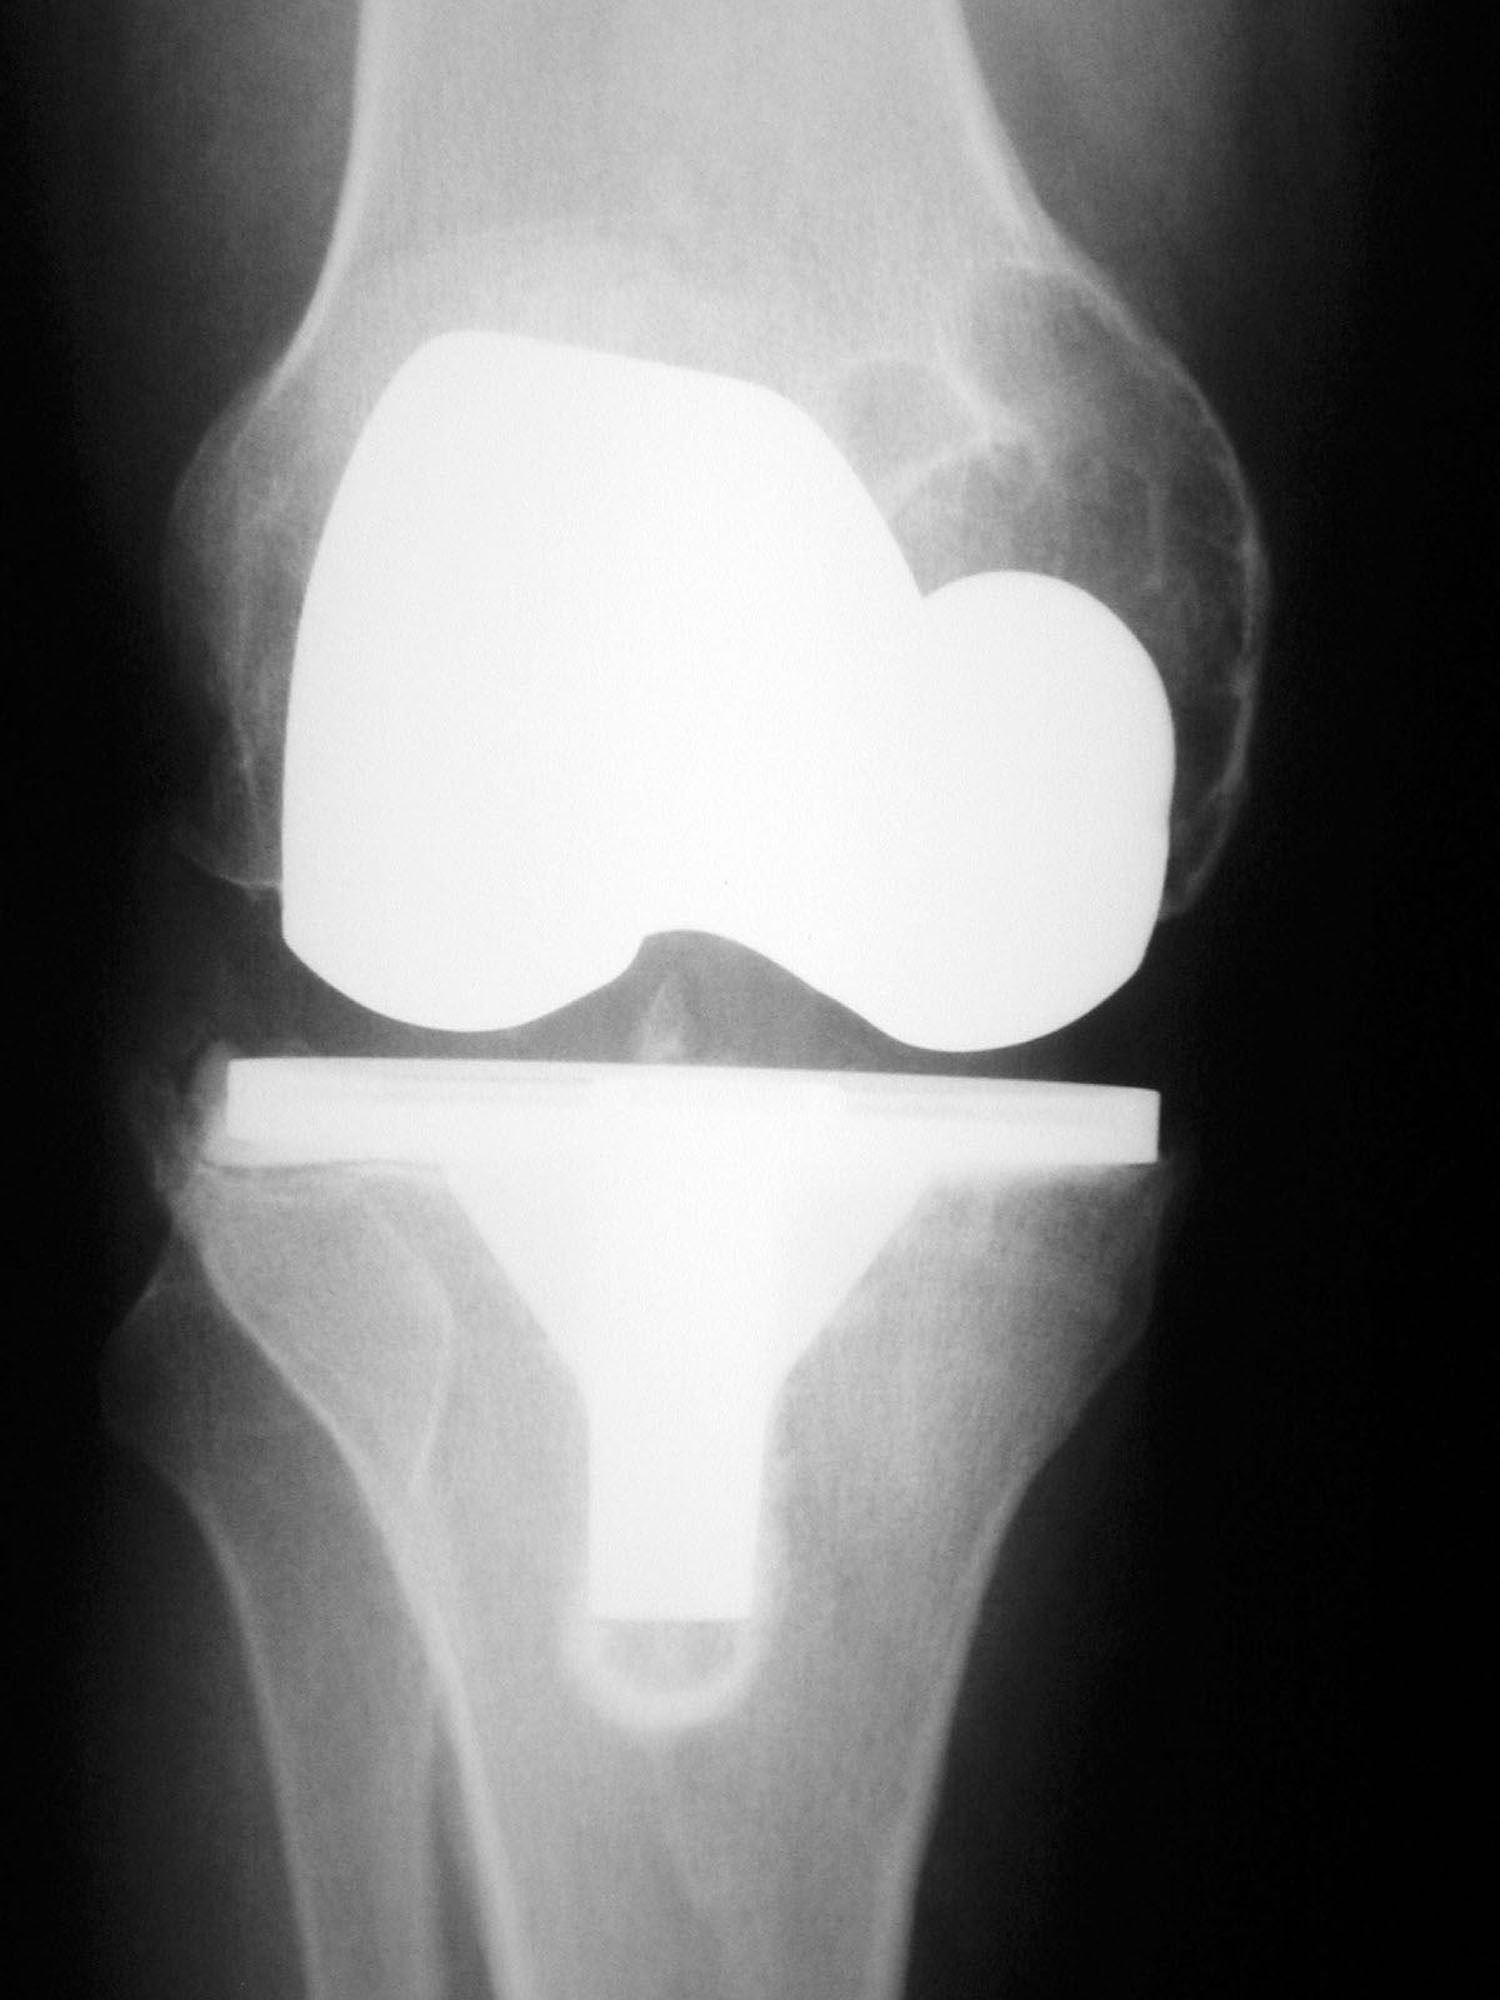

From www.researchgate.net

Aseptic loosening case. a Anteroposterior view; b Lateral view Aseptic Loosening Dental Implant Our preliminary study shows that porous implants (namely dental implants) made from titanium alloy by slm can be adequately. Moreover, implant surface treatments, pore size, pore density, and femoral stem design should be appropriately selected. In medicine, an aseptic environment is necessary and expected to. This osteolytic effect could be enhanced by vitamin d deficiency, since maier et al. Demonstrated. Aseptic Loosening Dental Implant.